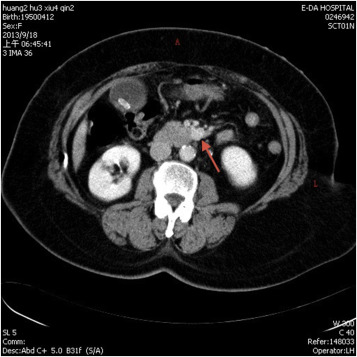

Transabdominal ultrasonogram demonstrated a hypoechoic mass (arrow) in the uncus ...

Transabdominal ultrasonogram demonstrated a hypoechoic mass (arrow) in the uncus of the pancreas.